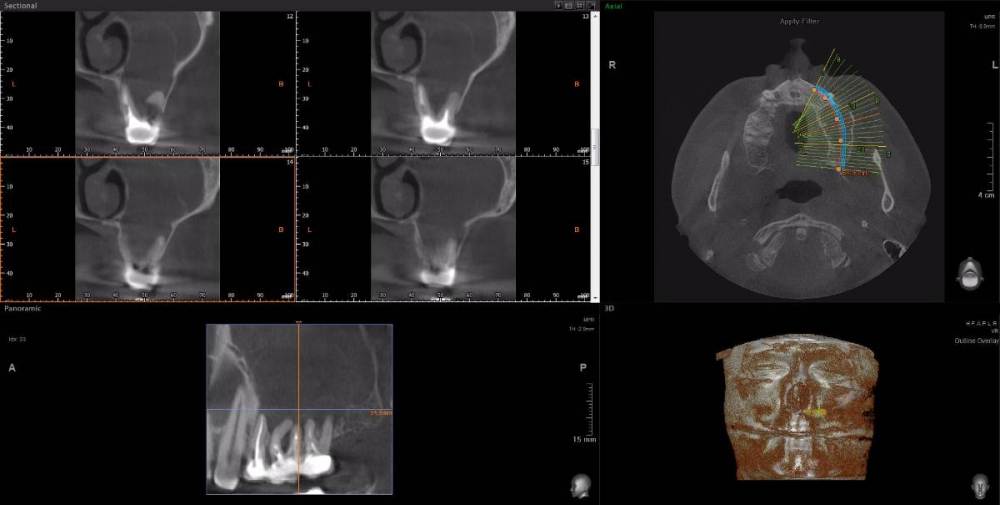

wladdX Опубликовано 22 марта, 2021 Поделиться Опубликовано 22 марта, 2021 При изучении КЛКТ, сделанной по другому поводу, обнаружил радикулярную кисту с врастанием в в/чел синус, размерами около 3*3*3см. Костных стенок кроме нижней и медиальной уже нет. Скрытый текст Как к этому делу подступиться правильно? Ссылка на комментарий

kriokov Опубликовано 23 марта, 2021 Поделиться Опубликовано 23 марта, 2021 3 часа назад, red_butler сказал: имхо, нужно через ЛОРа соустье по фронтальному срезу рабочим выглядит. Видно хорошо деформацию латеральной стенки по сравнению с противоположной стороной. Нет грубой деструкции. Удалить зубы причинные, цистэктомия , окно доступа закрыть мембраной или титаном. Ссылка на комментарий